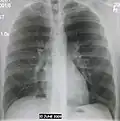

Normal AP CXR

AP CXR showing left lower lobe pneumonia associated with a small left sided pleural effusion -

AP CXR showing right lower lobe pneumonia -

AP CXR showing pneumonia of the lingula of the left lung -

Right upper lobe pneumonia as marked by the circle. -

Left upper lobe pneumonia with a small pleural effusion.

Right lower lobe pneumonia as seen on a lateral CXR